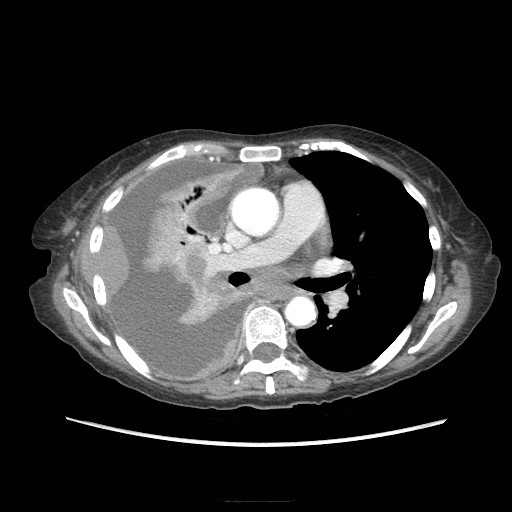

Gallery Pleural malignant effusion (pleural mets)

malignant effusion (pleural mets)